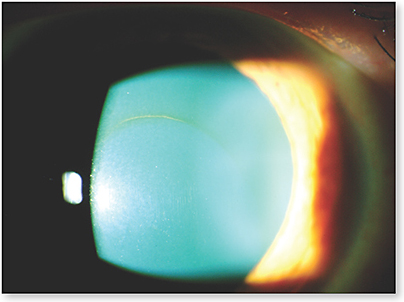

Кольцо Кайзера Флейшера Фото

Кольцо Кайзера Флейшера Фото 110 фотографий